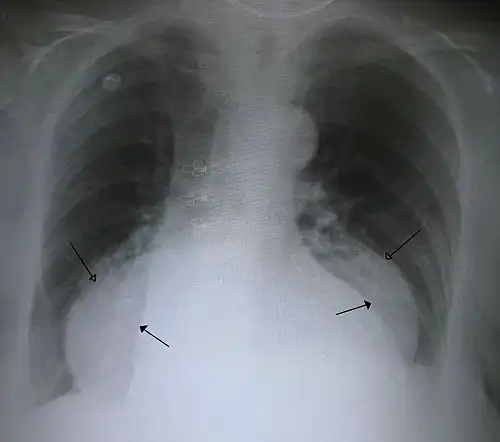

- A large hiatal hernia on chest X-ray marked by open arrows in contrast to the heart borders marked by closed arrows

This hiatal hernia is mainly identified by an air-fluid level (labeled with arrows). -